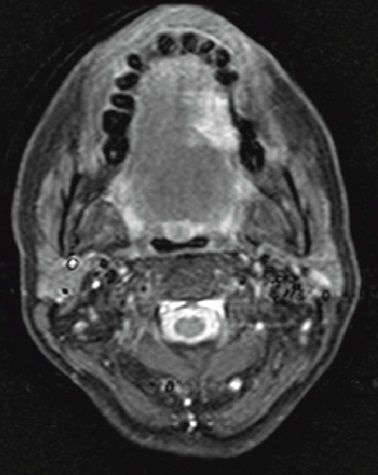

Voici l’un des examens que vous récupérez.

Question 8 : Que pouvez-vous dire à partir de cette coupe ?

Les structures sont symétriques, pas de ganglions visibles sur cette coupe

La lésion ne passe pas la ligne médiane : on constate la lésion en hypersignal à gauche et qui ne dépasse pas la ligne médiane fibreuse en hyposignal. On peut en déduire qu’il y a a priori de faibles chances d’avoir des adénopathies controlatérales. Cela a des conséquences thérapeutiques, par exemple de discuter un curage cervical uniquement homolatéral à la lésion

On ne constate pas d’invasion osseuse sur cette coupe. Cette proposition est d’autant plus fausse que l’IRM ne permet pas d’étudier l’os convenablement. Il faudrait voir le scanner pour affirmer l’absence de lyse osseuse

C’est une séquence T2, les liquides sont en hypersignal (liquide céphalo-rachidien), c’est également la séquence où les lésions sont le plus souvent en hypersignal (par fréquence). Cette coupe montre la lésion du bord libre de la langue à gauche en hypersignal, qui ne passe pas la ligne médiane. On n’observe aucune autre anomalie (pas d’adénopathies).